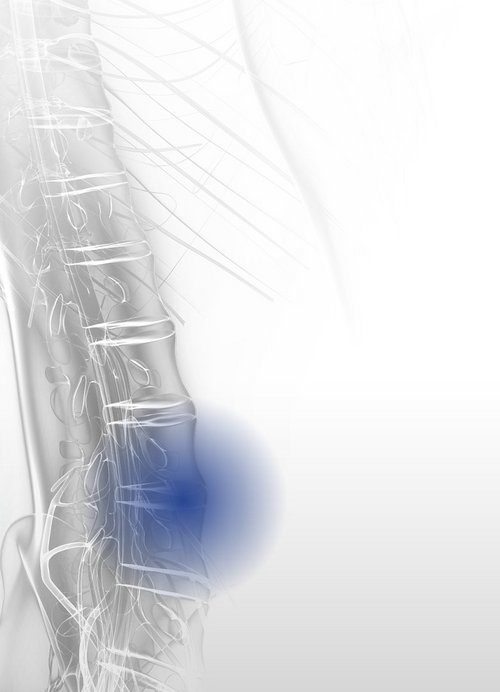

Discogenic pain syndrome is a degenerative spinal disease caused by wear and tear on vertebral discs. It begins with fluid loss in the inner core of the disc (nucleus pulposus), reducing its resilience and elasticity. This can lead to segmental instability. Sensitization of the affected area lowers the stimulus threshold, potentially resulting in chronic discogenic pain. Protruding discs may compress spinal and extraspinal nerve structures, causing radicular pain.